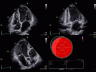

УЗИ аппарат Vivid E95 – это система 4D-сканирования премиум-класса, разработанная инженерами GE для наиболее сложных задач в области комплексной диагностической медицины. Синергия стационарной платформы Vivid и инновационной технологии cSound формирования ультразвукового луча позволяют добиваться потрясающих результатов в области сердечно-сосудистых исследований пациентов.

Vivid E95 – это интеллектуальная система, способная проводить различного рода обследования, благодаря усовершенствованным двухмерным и цветовым доплеровским изображениям. Теперь время, проведенное с пациентом, становится бесценным. Ведь количество неинформативных исследований снижается.

• Работа сканера во всех режимах 2D, 3D, 4D.